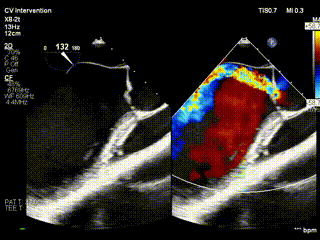

视频1:病例1术前食道超声示重度主动脉瓣反流

视频2:病例1术后心超示主动脉瓣无反流